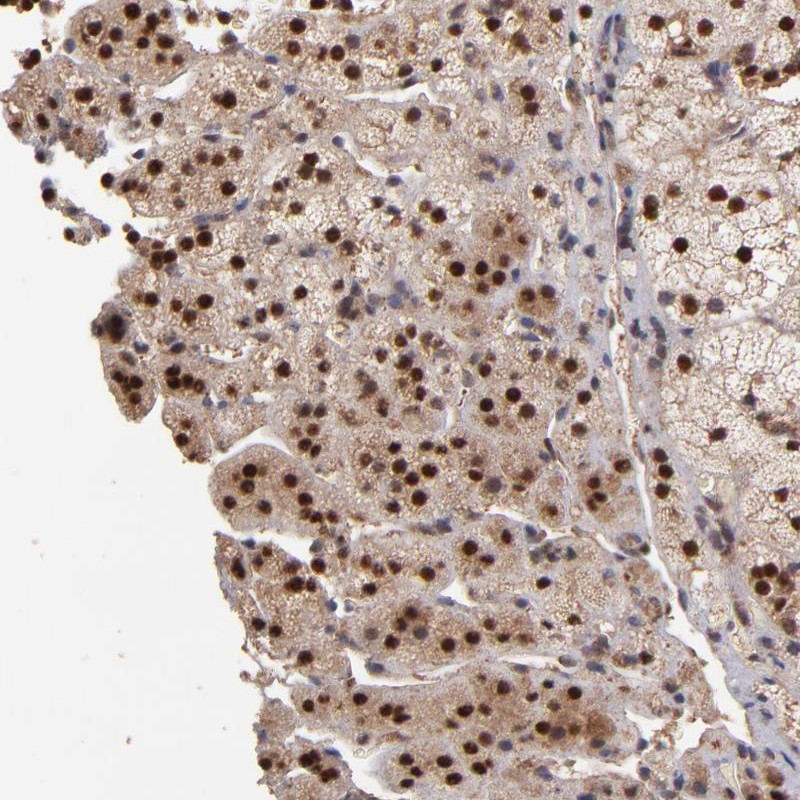

Immunohistochemical staining of human adrenal gland shows strong nuclear positivity in cortical cells.